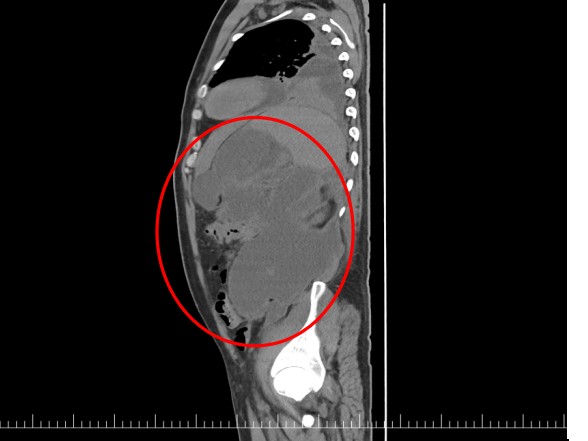

经过5天的全力救治,朱先生生命体征趋于平稳,转回普通病房后却再次出现反复发热。腹部CT检查提示:胰尾-左侧上下腹区巨大包裹性坏死形成,下缘达到直肠旁沟且呈多分隔状态。

常规“超声内镜引导下内引流”无法充分引流,病情再次陷入僵局,亟需更精准的救治方案。